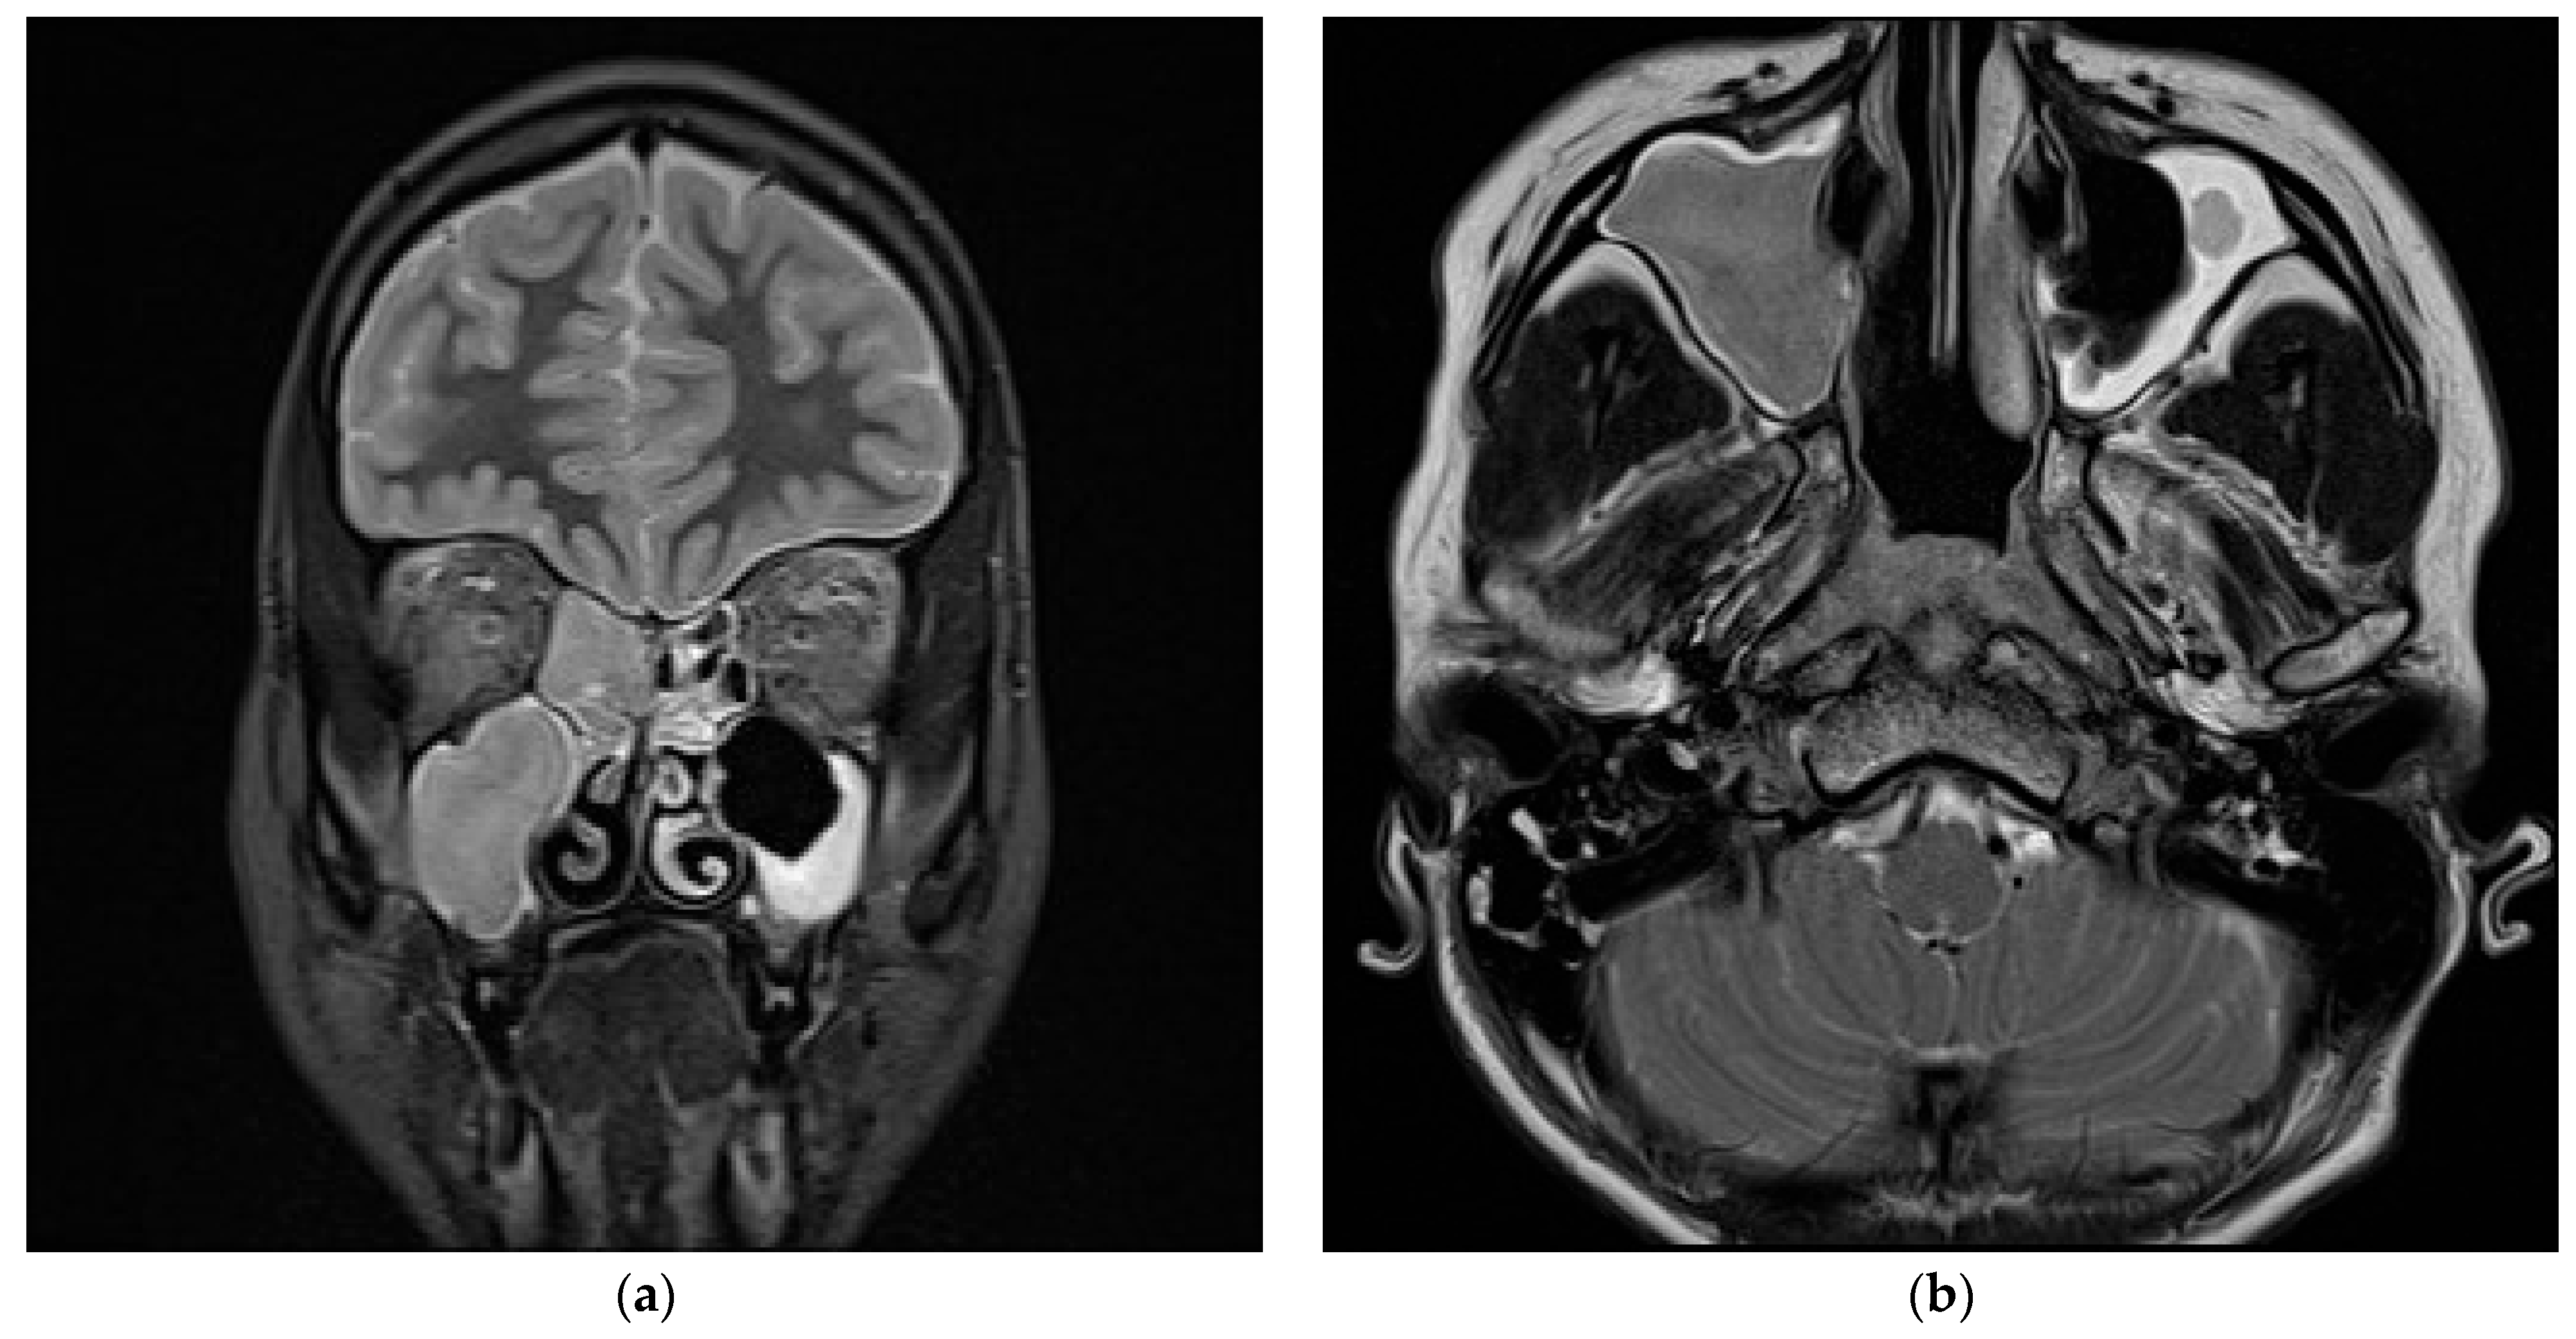

2.2.2. Initial Assessment and Hematological and Radiological Investigations

2.2.3. Microbiology Investigations